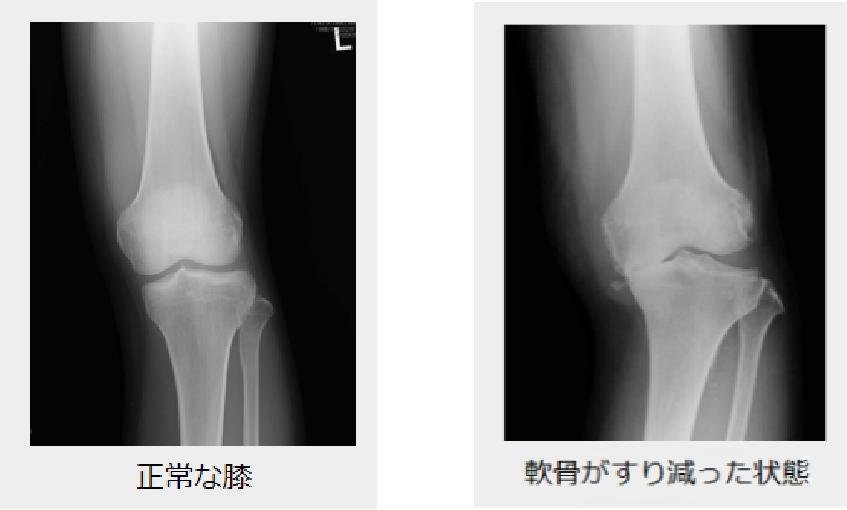

年齢とともに、大切な軟骨がすり減ってしまい、膝の関節の変形が進行すると、膝の痛みや腫れが出現し、薬で は治らなくなってしまいます。歩けなくなり始めると、筋肉や骨も弱くなり、増々悪くなる一方となります。

このような場合に人工関節手術を行うと、痛みが取れ、正座はできませんが、通常の生活や軽い運動ができるようになります。